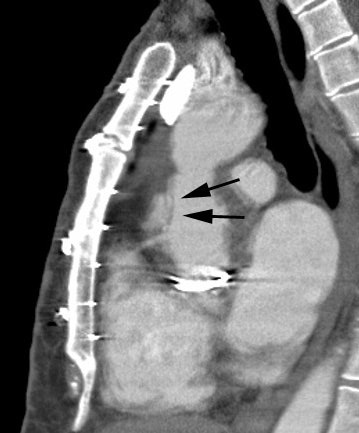

Hx graft repair of an ascending aortic aneurysm: A routine followup CT demonstrated a pseudoaneurysm arising from just above the right coronary artery graft site (black arrows). Surgical repair was performed. There was no evidence for infection. Click image to view cine file- note large amount of low attenuation between graft and native aorta. |